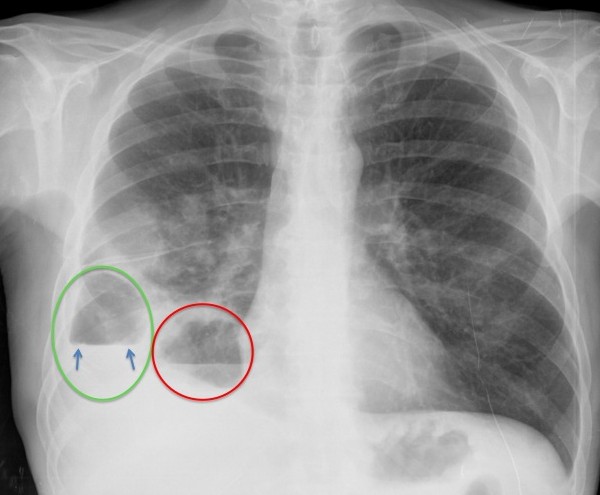

Veámos mejor.

En la placa PA, se observa un encapsulado pleural (verde) y una cavidad parenquimatosa (roo), ambas con nivel hidroaéreo. En el pleural, obsérvese la discordancia del nivel (flechas), tanto en longitud como en densidad, entre las dos proyecciones y borramiento de la pared superior y más posterior en la placa lateral. En la cavidad parénquimatosa, se conserva la misma forma y densidad en las dos proyecciones, con delimitación del controno superior de su pared.